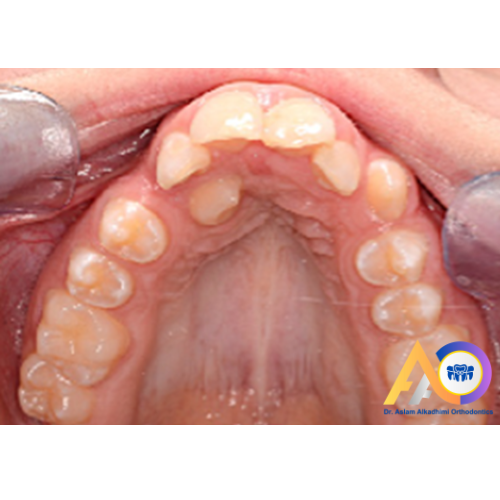

Pre-treatment: UR3 impacted palatally, not particularly high.